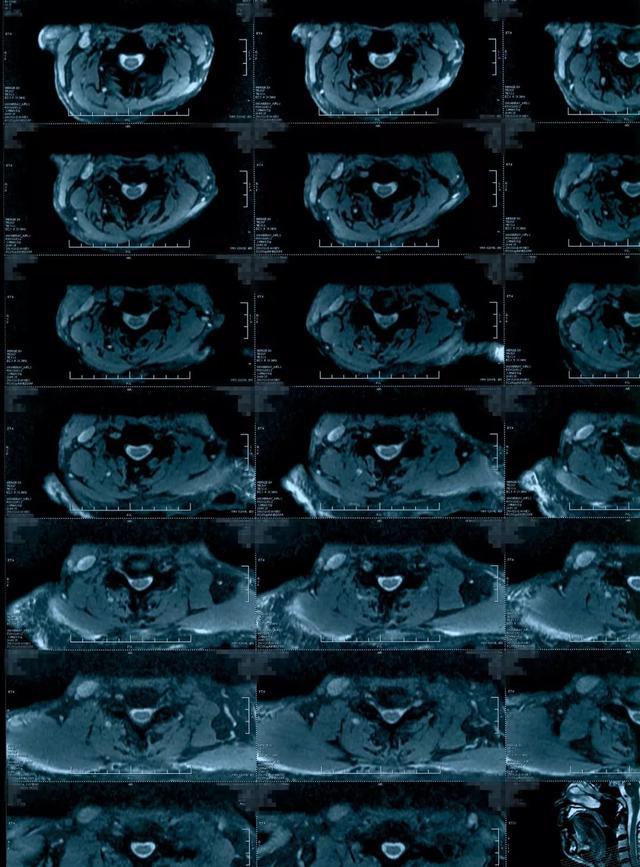

颈髓水肿

颈髓水肿,颈髓

音频病例点评椎管狭窄脊髓水肿该怎么治疗